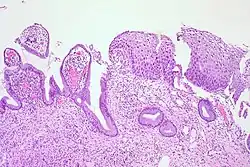

Normal cervical epithelium

Historically, abnormal changes of cervical epithelial cells were described as mild, moderate, or severe epithelial dysplasia. In 1988 the National Cancer Institute developed "The Bethesda System for Reporting Cervical/Vaginal Cytologic Diagnoses".[12] This system provides a uniform way to describe abnormal epithelial cells and determine specimen quality, thus providing clear guidance for clinical management. These abnormalities were classified as squamous or glandular and then further classified by the stage of dysplasia: atypical cells, mild, moderate, severe, and carcinoma.[13]

Depending on several factors and the location of the lesion, CIN can start in any of the three stages and can either progress or regress.[1] The grade of squamous intraepithelial lesion can vary.

CIN is classified in grades:[14]

Histology Grade Corresponding Cytology Description Image

CIN 1 (Grade I) Low-grade squamous intraepithelial lesion (LSIL)

• Mild epithelial dysplasia

• Confined to the basal 1/3 of the epithelium

• Typically corresponds to infection with HPV

• High rate of regression back to normal cells

• Usually managed expectantly